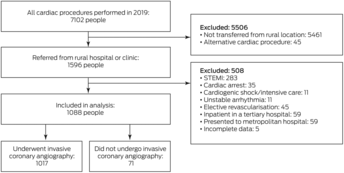

Of 1596 people from rural or remote WA referred for ICA in Perth during 2019, 508 were ineligible for our study and 71 did not undergo ICA (Box 2). The mean age of the 1017 people who underwent ICA was 62 years (SD, 13 years), 680 were men (66.9%), and 245 were Indigenous people (24.1%) (Box 3). A total of 411 people were referred for ICA as elective outpatients (40.4%). Of the 606 people transferred between regional and Perth hospitals (inter‐hospital transfers; 59.6%), the indication was NSTEMI in 425 cases (70.1%) and chest pain with normal troponin levels in 132 (21.8%).

Box 2 – People in rural or remote Western Australia assessed for cardiac condtions during 2019: selection for inclusion in our study

STEMI = ST‐segment elevation myocardial infarction.